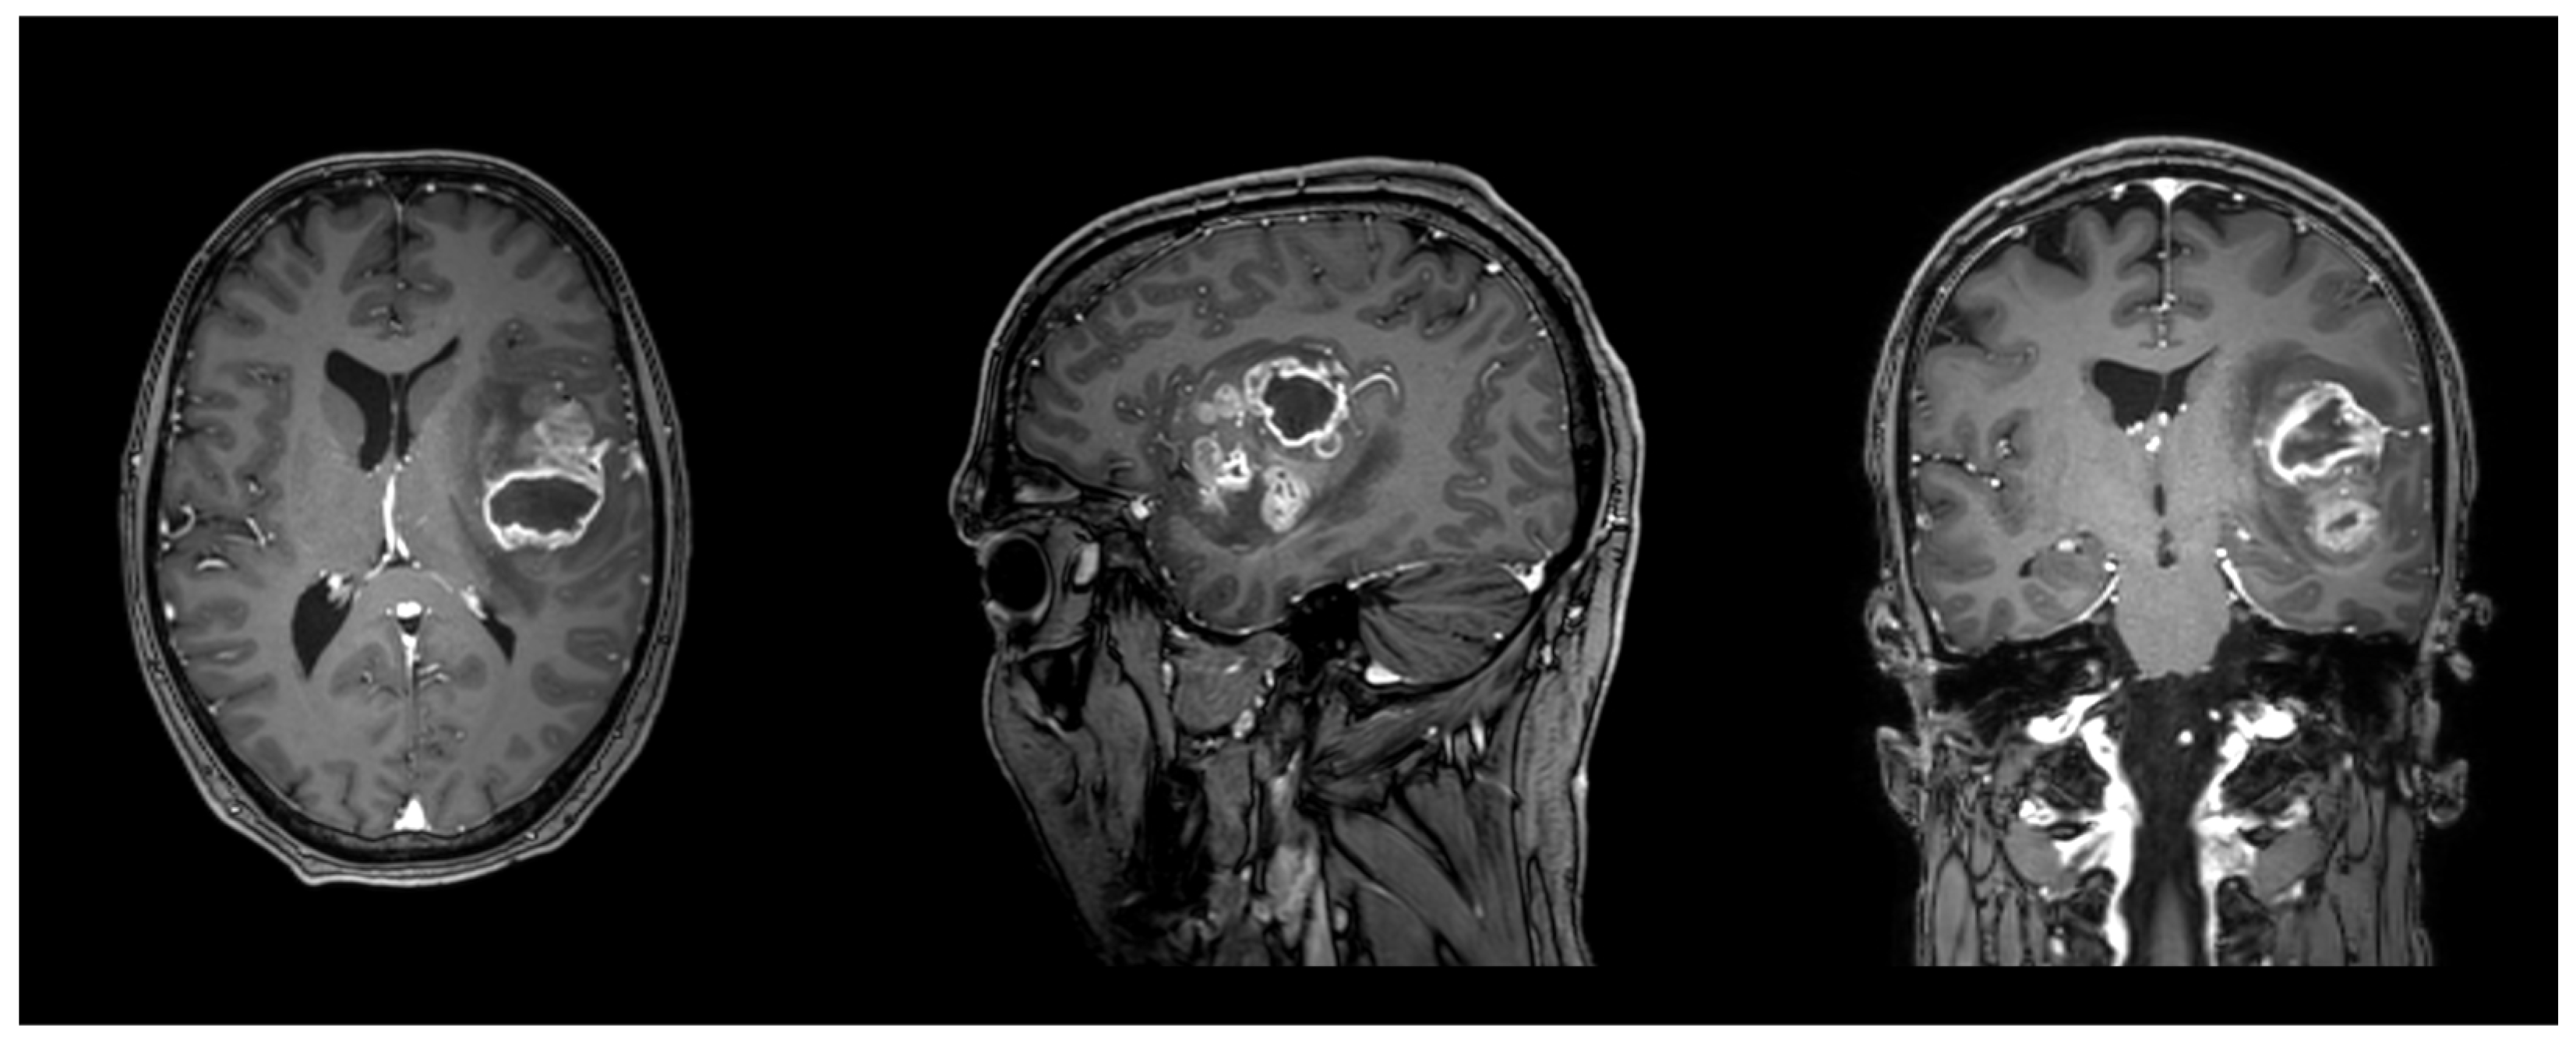

One patient was lost to follow-up. With respect to tumor location, the majority of lesions involved the left hemisphere (n = 19), most frequently affecting the temporal (n = 9) and frontal lobes (n = 3), whereas right hemispheric tumors (n = 18) were predominantly located in the frontal (n = 6) and temporal lobes (n = 5). One case demonstrated corpus callosum involvement. With regard to the issue of laterality. The present investigation is exclusively focused on the issue of lesion laterality. The distribution of responses is as follows: In the present study, 27 patients were analyzed and the results indicated that nine of these patients (33.3%) were classified as left-only, eight patients (29.6%) were classified as right-only, and 10 patients (37.0%) were classified as bilateral. The lobar distribution data presented in Table 1 are non-exclusive, meaning that a tumor may involve multiple lobes and/or both hemispheres. Detailed demographic data, tumor characteristics, and neuroanatomical locations are summarized in Table 1. An illustrative case can be found in Figure 2.

Figure 2. Illustrative case of a male patient in his forties with a left frontotemporal glioblastoma, WHO grade 4, IDH wildtype, MGMT promoter not methylated, EGFR amplified. FA in the left AF was 0.42, and 0.38 in the left FAT. T1 sequence with contrast enhancement. Planes are in radiological orientation, from left to right: axial, sagittal, coronal.